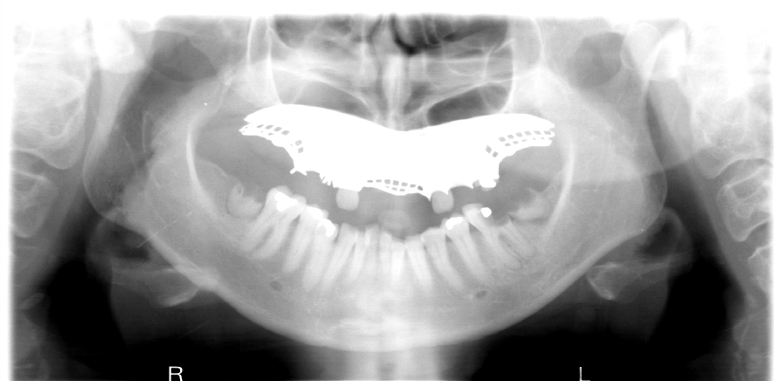

What is wrong with this image?

Inferior turbinates and meati spread across maxillary sinuses (too far back)

(also ghost image of earrings?-haley)